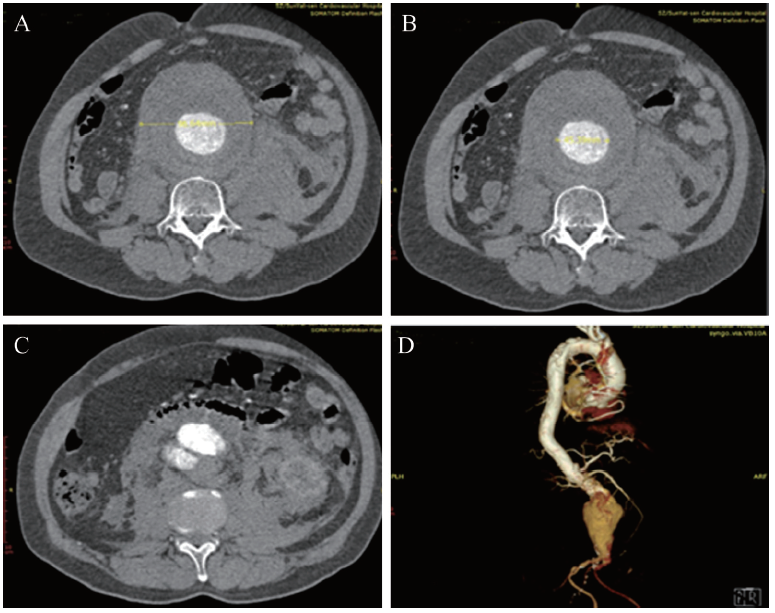

血常规示血红蛋白90 g/L,白细胞12.7 ×109/L,红细胞2.9×1012/L,血小板143×109/L。UCG示LVEF 0.55,心腔结构未见异常。全主动脉增强CT扫描提示腹主动脉瘤并腹主动脉破裂。术前CT血管三维重建显示患者肾下腹主动脉呈囊性扩张。瘤体最大直径约96 mm,瘤体真腔最大直径约45 mm,瘤体破口位于右侧肾动脉以下,瘤颈向右侧略偏斜,无明显扭曲,长度约15 mm,见图1

图1 一例腹主动脉瘤患者入院当日的CTA图像

A~C:轴位图像,D:VR容积成像显示侧位图像